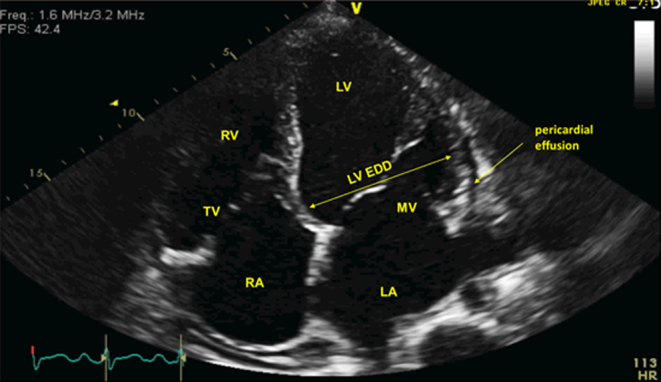

Echocardiography revealed features of severe dilated cardiomyopathy (DCM) with a left ventricular EF of 12% and spherical heart geometry (Fig. 1). Comprehensive investigations (including coronary angiography, cardiac MRI and cardiomyopathy screen) ruled out other causes for DCM. EF partially recovered to 28% after definitive treatment of Graves’ disease.

Figure 1.

The long axis four chamber echocardiographic view of the heart shows biventricular dilatation (RV EDD: 5.5 cm, LV EDD: 6.6 cm) with severe LV systolic dysfunction (EF 10–15%), moderate-severe functional mitral regurgitation and no wall motion abnormalities. These features are consistent with a non-ischaemic dilated cardiomyopathy. EDD (end-diastolic diameter): 6 cm, ESD (end-systolic diameter): 4.8 cm, ESV (end systolic volume): 201 mL, EDV (end-diastolic volume): 261 mL, IVS (intraventricular septum wall thickness): 0.7 cm, PW (posterior wall thickness): 0.9 cm, RWT (LV relative wall thickness): 0.3 cm, calculated EF 23%, LA volume 62 mL, LV wall mass 186 g, LV mass index 96 g/m2, PAP = no TR jet. RV, right ventricle; LV, left ventricle; EDD, end-diastolic diameter; EF, ejection fraction.